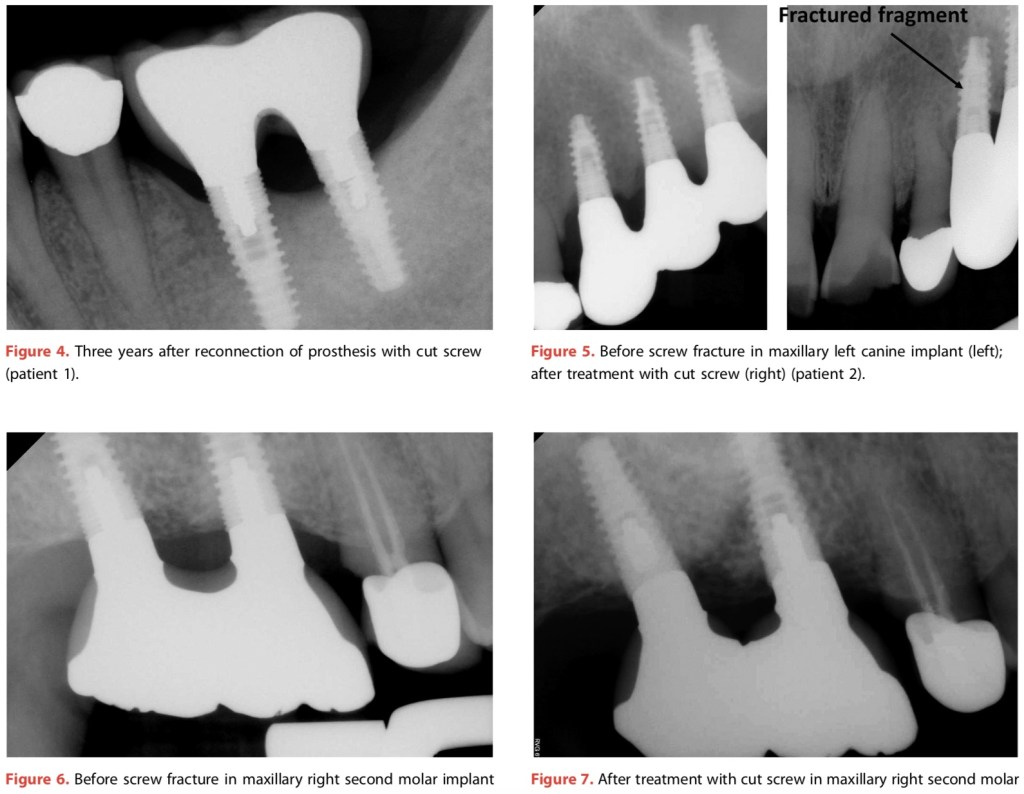

另類拯救Abutment screw fracture的方式—Yi(2021)

這篇敘述臨床abutment screw fracture的狀況,應該是有在做植牙假牙醫師不想面對的事。那解決的方法很有趣,就是乾脆將斷掉的部分向內推,然後換一支截斷的screw。而且最好要跟隔壁植牙相連(那單顆的可以嗎?)

雖然不希望會遇到這樣的狀況,但是看看別人怎麼做的總是很有趣的。